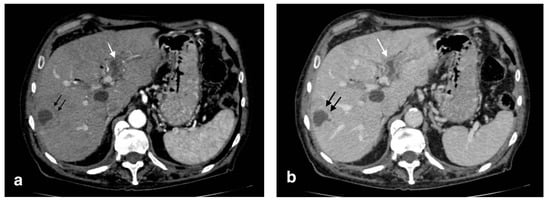

Acute portal vein thrombosis is an uncommon condition caused by the formation of a thrombus within the portal vein, as the inflammatory insult persists. Besides acute cholecystitis, it could be diagnosed as a complication of many other conditions, such as diverticulitis, urinary and pelvic infections, and malignancies [23,24]. Symptoms may be subtle, often masked by the underlying condition. CT and US are the main modalities for the acute assessment of PVT. The lack of enhancement within the vein lumen and an enlarged portal vein are the two main classic imaging CT features [24,25]. CT, unlike US, is also able to evaluate the extension of the thrombus and to detect associated findings, such as hepatic hyperemia (Figure 10), or complications, such as enteric ischemia or intra-abdominal collections [24]. Suppurative thrombosis of the portal vein, also known as pylephlebitis, is a life-threatening condition that requires early diagnosis and therapeutic assessment. The exact pathogenesis is not well known, but it is proven that specific bacterial species, such as Bacteroides Fragilis, play a key role in favoring a protrombothic state [26] and the clinical features of sepsis. As regards PVT, CT evaluation is meaningfully superior to ultrasonography for the diagnosis. Consequent to hepatic artery overflow due to PVT occlusion, transient contrast enhancement of the adjacent hepatic parenchyma during the arterial phase may occur, as well as hepatic microabscesses (Figure 11) [27]. Although not seen in most cases, CT may detect the presence of air within the thrombus as a hypodense focus within the thrombosed PV [24].

Figure 11.

Pylephlebitis in cholecystitis exacerbation: (a) massive thrombosis of the portal bifurcation with hyperdensity of portal walls due to pylephlebitis (white arrows) and inhomogeneous attenuation of liver parenchyma in arterial CT scan due to vascular occlusion; (b) axial scan: irregular thickening of cholecystic walls with contrast enhancement of liver parenchyma due to pericholecystic edema.